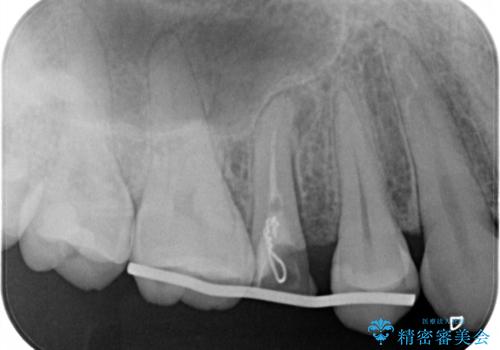

右上の被せものを除去したところ、中で歯が割れていたため、部分矯正で引っ張り出すことになりました。

歯を引っ張り出したり、歯肉の手術の経過待ちの間に、患者様のご希望で他の歯の虫歯治療も行いました。

・約3か月ほど引っ張り出します。

・両どなりの歯に一時的にワイヤーを接着します。

・十分に引っ張り出した後、歯肉の手術が必要となります。

・歯肉が落ち着いてから最終的な被せものの製作となります(約3か月)。

・歯の割れ方によっては引っ張り出す対象外となります(抜歯になります)。